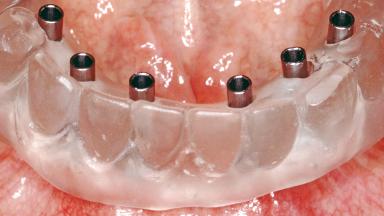

Conventional Loading of Six Implants in the Mandible and Final Restoration with a Full-Arch Metal-Ceramic FDP

A 68-year-old, completely edentulous male patient presented for evaluation and treatment options. He reported excellent general health and was taking no regular medication. He had been edentulous for approximately 12 years, having lost his teeth to periodontal disease and dental caries. The patient’s chief complaint was incompetent function. His secondary concerns included his appearance and the desire for a predictable outcome. He attributed his reduced functional capacity to his lower complete denture, which he described as poor. He was particularly concerned with the denture’s instability and poor fit. In general terms, he was satisfied with the maxillary complete prosthesis. The maxillary prosthesis was characterized by adequate retention, stability, and support, although the fit was considered less than ideal.

# of Implants 6

Type of Implants One-Piece

Attachment One-Piece

Prosthesis Type FDP